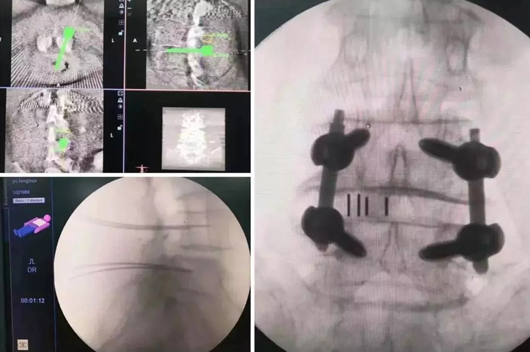

9.jpg

▲  天玑? 辅助脊柱侧后凸畸形手术

10月15日,,,,,,脊柱外科(骨肿瘤偏向)李建民教授团队也不甘示弱,,,,,,由李振峰教授主刀,,,,,,在天玑? 的辅助下完成了股骨转子位置肿瘤挖除后骨盆外架的装置牢靠,,,,,,骨盆外架装置时,,,,,,螺钉要求间距等宽,,,,,,徒手很难一次性完成植入,,,,,,有了天玑? 的助力,,,,,,指哪打哪。。。。。

10.jpg